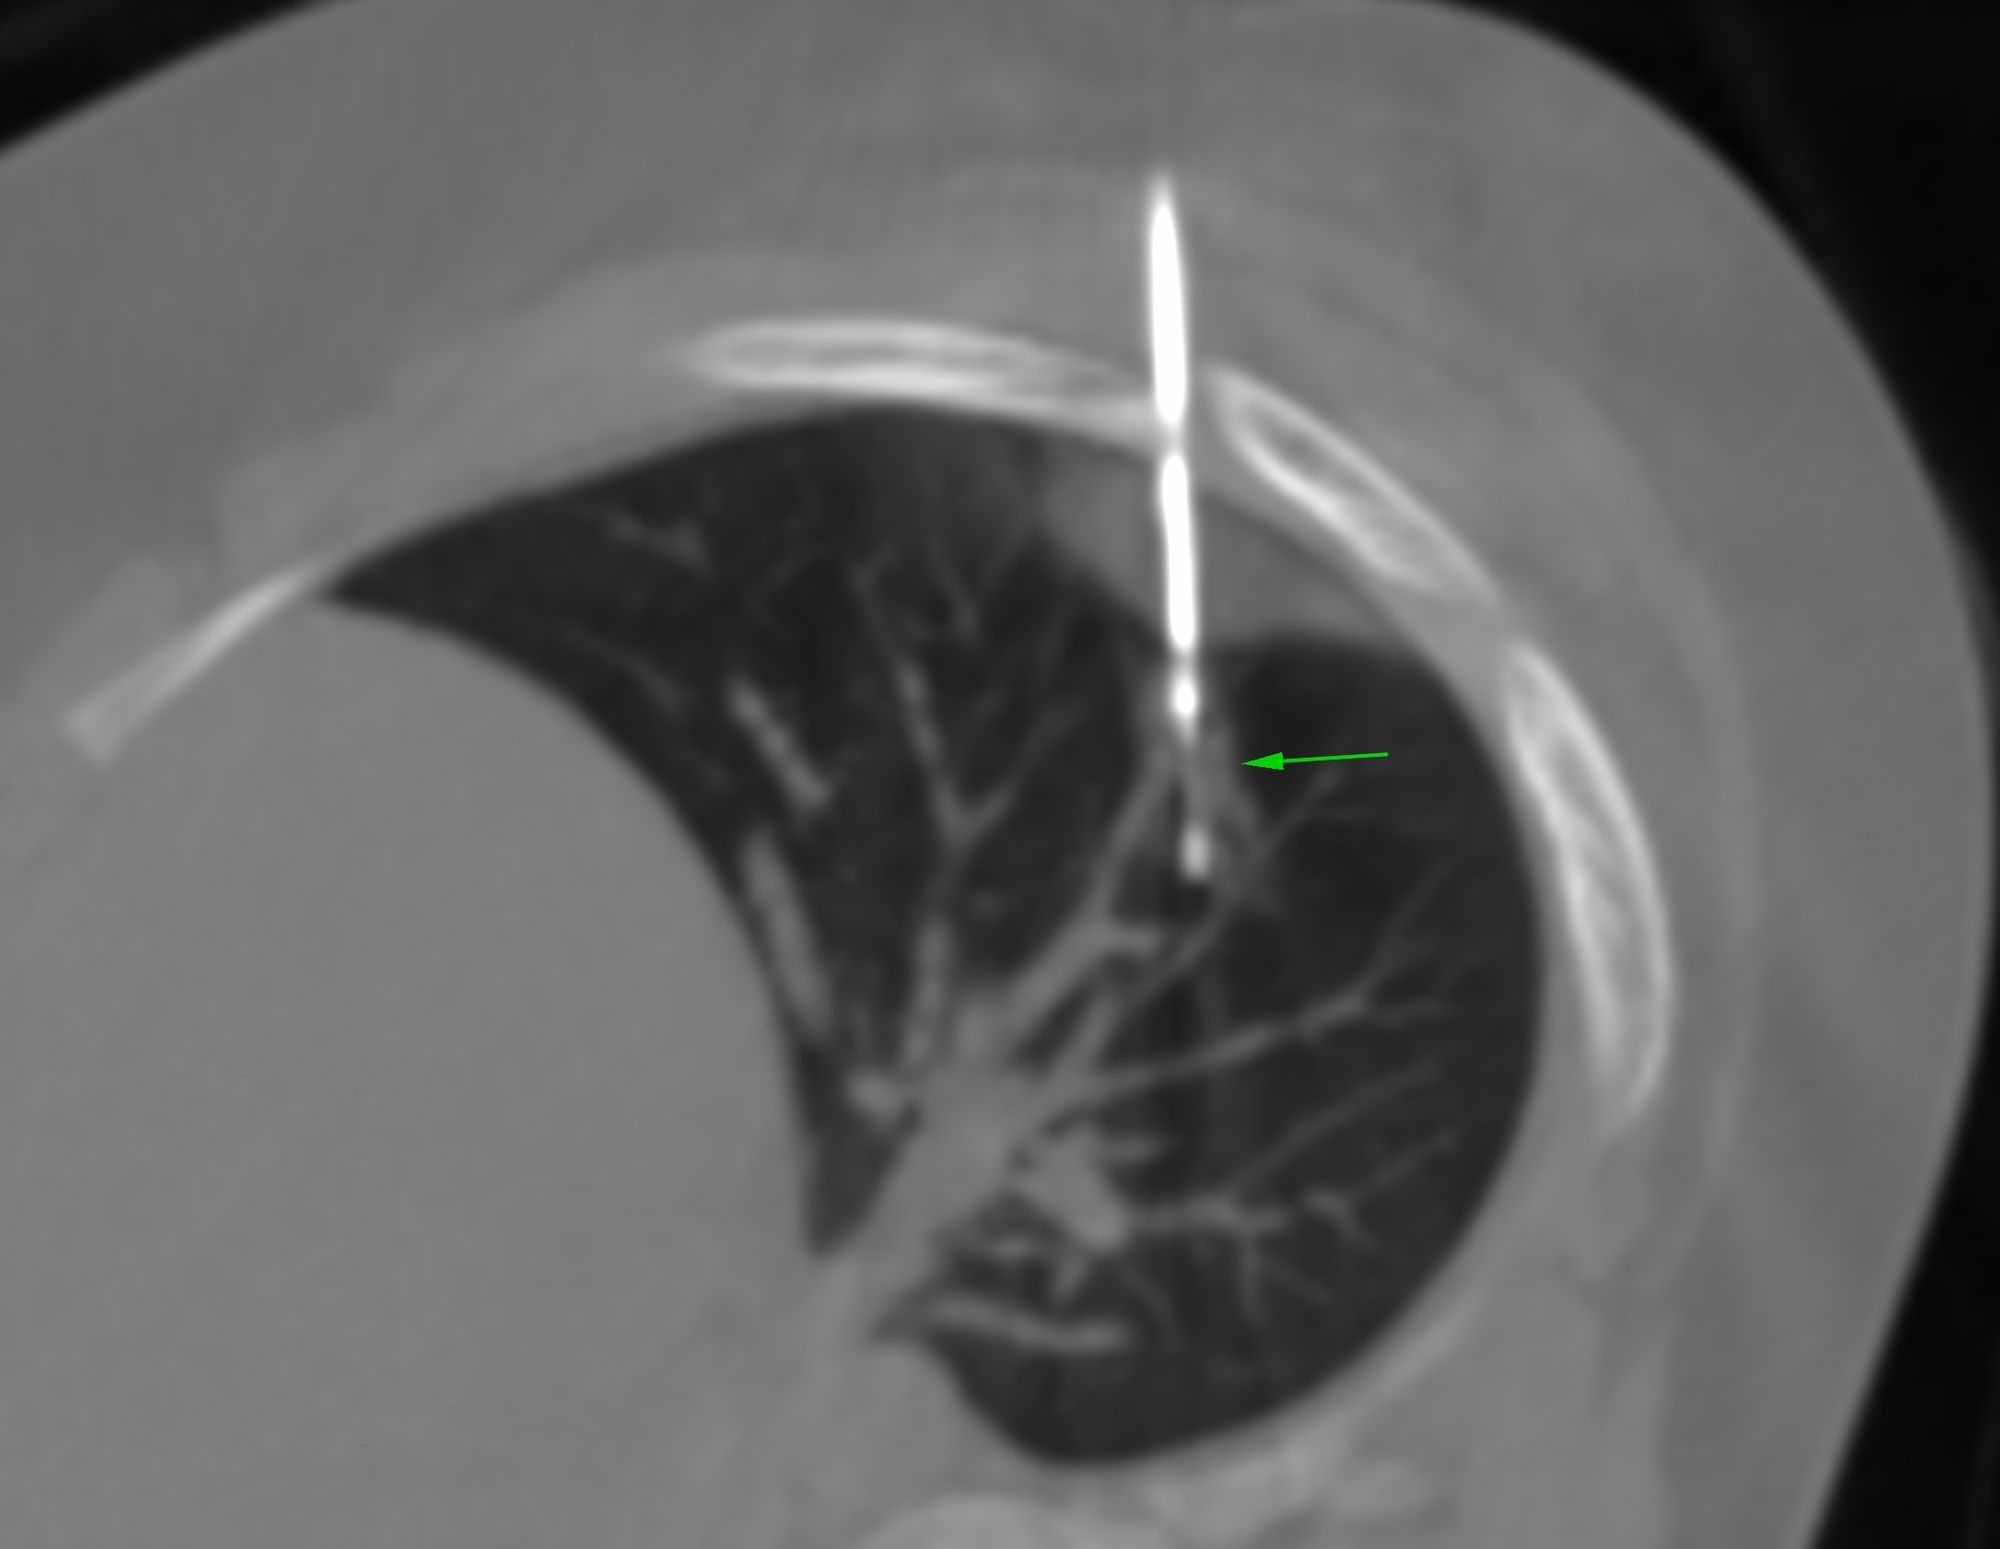

Case 17: 15 mm Lung Nodule Biopsy - Multiple Lung Nodules

Bhavin Jankharia - 28 March 2021